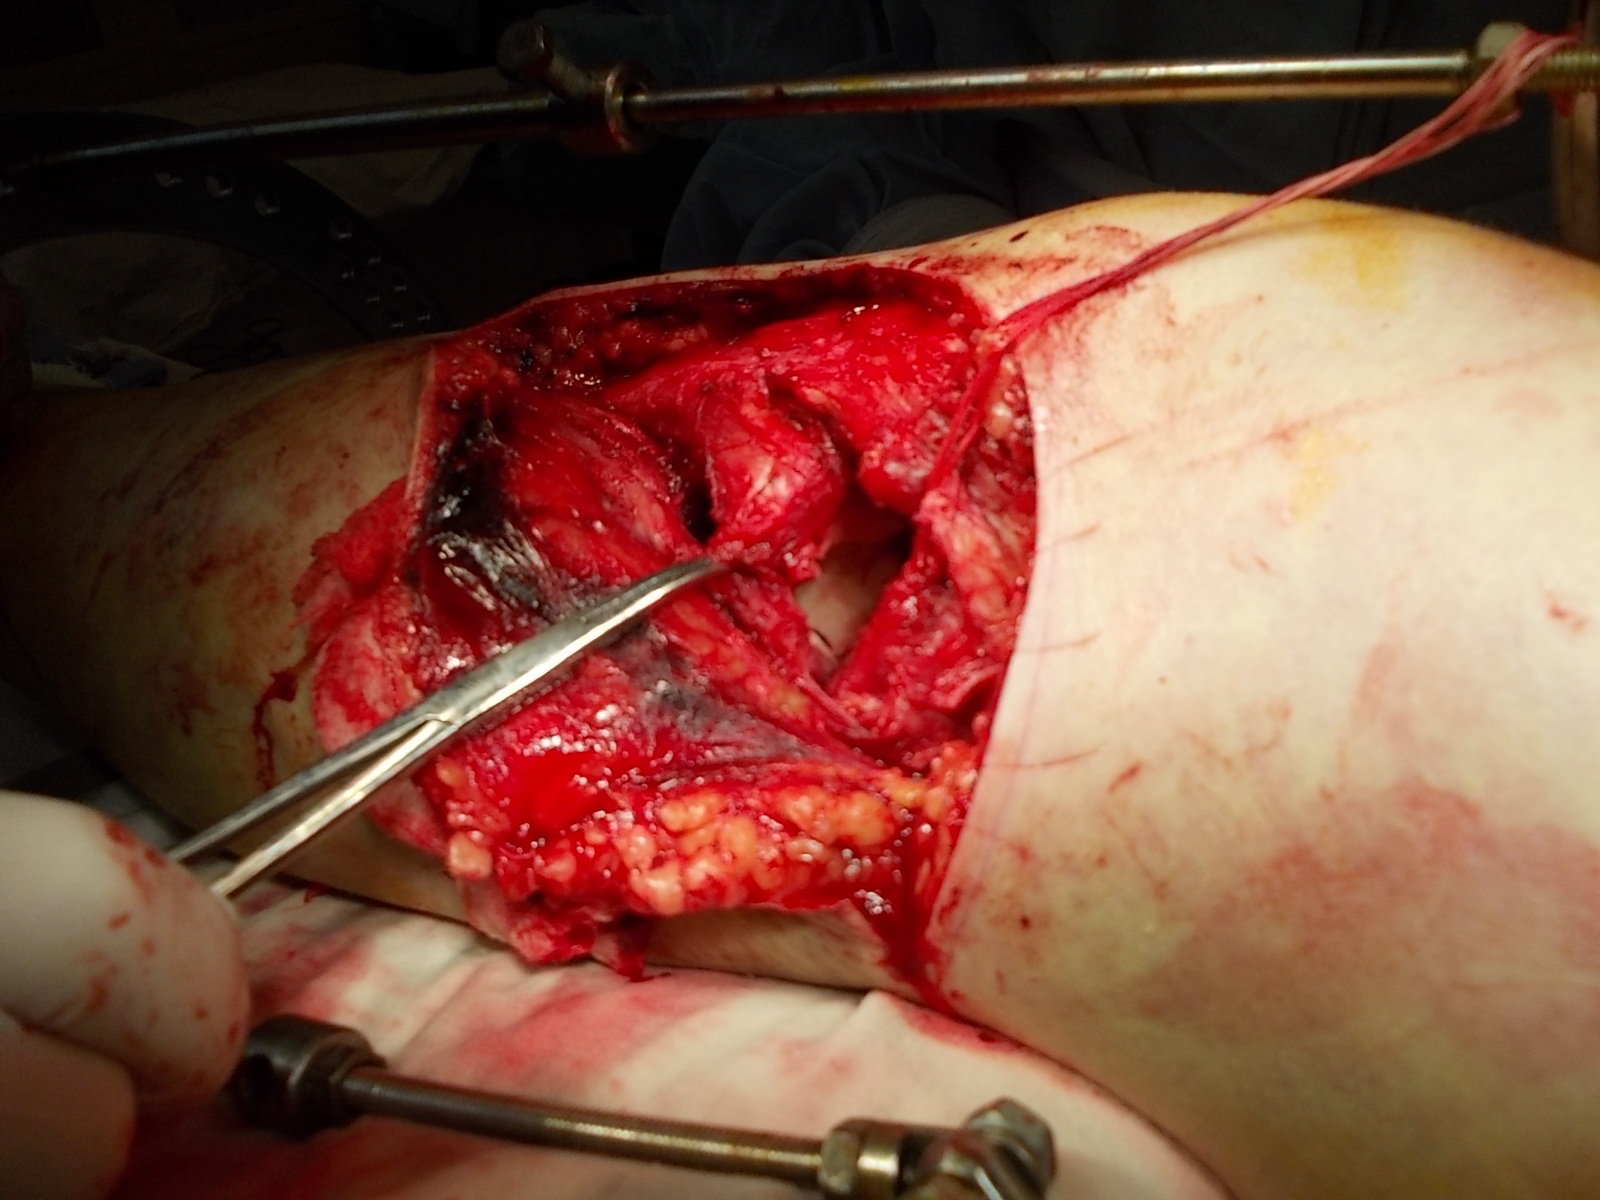

Операция - открытая репозиция, остеосинтез большеберцовой кости опорной пластиной с костной ксенопластикой маетриалом "Остеоматрикс". На контрольных снимках в три и шесть месяцев имеется консолидация перелома, миграции фиксатора нет, имеется остеоинтеграция ксенопластического материала. Функция коленного сустава полная.

Отдаленные результаты через 3 (три) месяца

Отдаленные результаты через 6 (шесть) месяцев

Отдаленные результаты через 14 (четырнадцать) месяцев